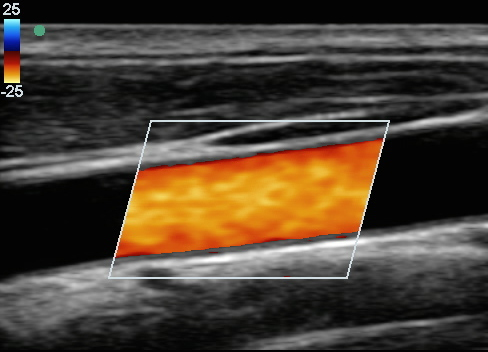

颈动脉颈总动脉 (CCA) 彩色 2 图像